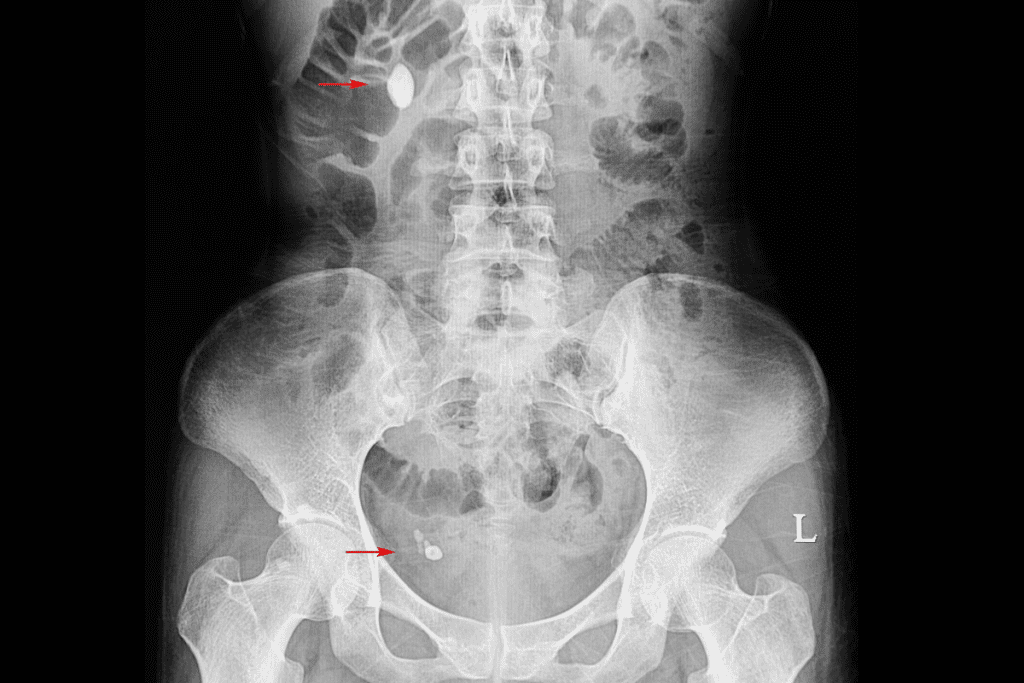

Diagnostic Methods

Diagnosing gallstones involves imaging tests and clinical checks. Ultrasound is the main tool, as it can spot gallstones and check the gallbladder’s function. Other tests, like CT scans or MRIs, might be used if complications are suspected.

A gallstone on ultrasound looks like a bright echo in the gallbladder. It often has shadowing behind it. Accurate diagnosis is key to the right treatment, such as a cholelithiasis operation.

ESWL is a medical treatment that uses shock waves to break down stones. These shock waves come from outside the body. They are aimed at the stones using X-ray or ultrasound.

- Imaging technology helps target the stones accurately